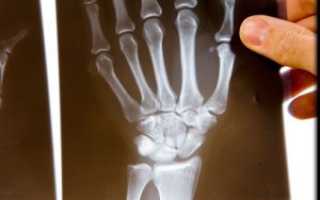

- 5) Поражение суставов кисти;

- 7) Характерные рентгенологические изменения.

Суставы, поражение которых, наряду с другими симптомами, указывает на ревматоидный артрит:

- между пястными и фаланговыми костями на II и III пальцах рук;

- между первой и второй фалангами на стопах;

- лучезапястные;

- локтевые;

- коленные;

- голеностопные.

- типичной картиной поражения суставов (по их внешнему виду и рентгенологически);